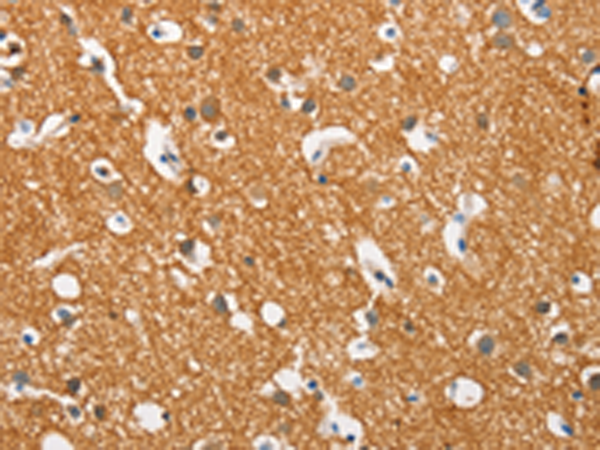

分类: 科研抗体货号: P11572别名: PD1; NACP; PARK1; PARK4应用: IHC反应种属: Human, Mouse, Rat